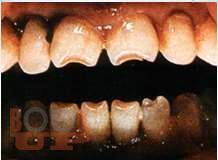

В пособии представлены вопросы этиологии, клиники, диагностики, лечения зубочелюстных аномалий и методы их комплексной профилактики.

Включает в себя тему изменений в околозубных тканях в процессе ортодонтического лечения, описаны ортодонтичекие силы, различные теории перестройки костной ткани, изменения в ВНЧС при перемещениях нижней челюсти. Описаны причины рецидивов как таковых, так и отдельных нозологических форм зубочелюстных аномалий, а так же рекомендации для надежного ретенционного периода и уменьшению рисков возникновения рецидива. Учебное пособие предназначено для студентов, обучающихся по специальности 31.05.03 «Стоматология».